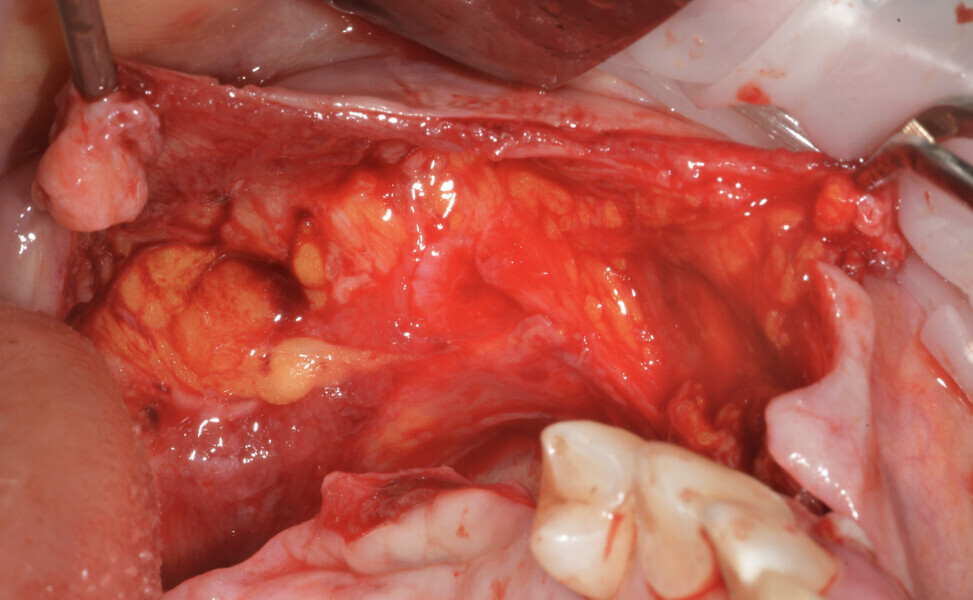

On the day of implant surgery, a para-crestal horizontal incision was made to expose the mesh and remove it, after the removal of the titanium screws and the new bone that had formed over the mesh (Figs. 25a & b, 26). Clinical examination showed complete regeneration of the vertical defect and the absence of pseudo-periosteum or thin pseudo-periosteum (< 1 mm), corresponding to the pseudo-periosteum Type 1 according to the Cucchi classification (Figs. 27 & 28).20